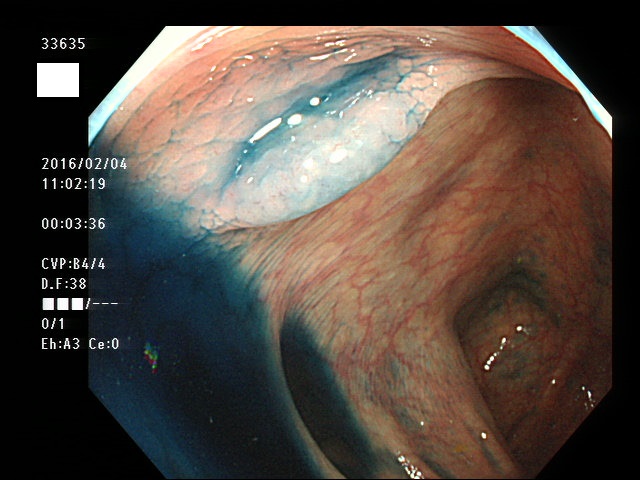

上記100名より抽出した平坦・陥凹型腺腫(=癌化の危険が高いが見落としやすい病変)の内視鏡写真

33627 33628 33629 33630 33631 33633 33635(SSA/Pのみ) 33638 33640 33641 33642 33643 33649 33653 33654 33656 33657 33660 33662